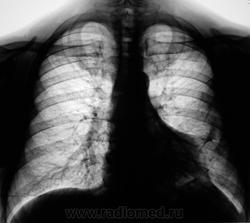

Уменьшение пневматизации нижней доли, плевро-медиастино-диафрагмальные спайки, деформация диафрагмы, средостения-больше данных за посттравматические изменения органов грудной клетки, + диафрагмальная грыжа.

Понял, а не допускаете мысли, что могла быть операция на лёгком с резекцией ребра ( хорошо виден фрагмент заднего отрезка V ребра слева, с абсолютно нормальной костной структурой, что нехарактерно для метастатического поражения ребра ).

Нарушение проходимости "среднедолевого или их?" бронха слева, гиповентиляция язычковых сегментов, тень в верхнем средостении. Центральный рак.

Коллеги, не вижу V ребра слева ( это мне подсказал, коллега который просматривает сайт). Как это расценивать?

Очаги то посттуберкулёзные, или как?

Стопудово центральный рак?